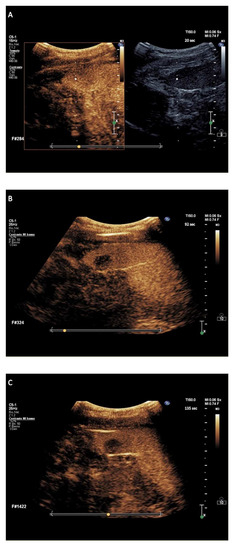

2.2.2. Splenic CEUS Patterns

2.2.3. Splenic CEUS Test Positivity

| Sarcoidosis, n = 20 | 1.5 (0.5–2.2) | Globally, hypoechoic compared to the surrounding parenchyma | Globally, hypoechoic (without later washout) compared to the surrounding parenchyma | Lymph nodes biopsy plus imaging follow-up after treatment, n = 20 |

| Hemangiomas, n = 20 | 1.5 (1.1–6) | Isoenhancement (n = 10), capillary hemangiomas Discontinuous globular peripheral enhancement (n = 10), cavernous hemangiomas | With or without later washout of mild degree as intensity (n = 10), capillary hemangiomas Progressive centripetal fill-in or very late (>3 min) washout of mild degree (n = 10), cavernous hemangiomas | Clinical and imaging follow-up, n = 20 |

| Abscesses, n = 10 | 1.1 (0.7–1.5) | Thin rim hyperenhancement pattern | Washout | Blood culture, n = 10 (positive test for fungus, n = 8; positive test for bacteria, n = 2) plus imaging monitoring after anti-microbial therapy |

| G-CSF-related myeloid metaplasia, n = 4 | 2.5 (2–3.2) | Relative hypoenhancement of the periphery of nodule and normal enhancement in the remaining portion of lesion compared to the surrounding parenchyma (reversed rim-enhancement) | Isoenhancement | Clinical and imaging follow-up, n = 4 |